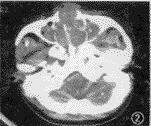

图2 鼻腔非霍奇金淋巴瘤,双侧鼻腔及上颌窦肿物,左翼腭窝受累,左上颌窦后外侧壁见小范围骨质缺损

2.病灶形态及密度:8例病灶以增殖为主,呈肿块状(图2,3),其中6例合并浸润,1例鼻翼明显溃烂(图4)。3例以浸润为主,表现类似黏膜增厚或鼻翼增厚(图5),其中2例弥漫浸润(图6)。CT值23.1~59.8 HU,增强后最高达88.6 HU。肿块密度相对均匀,浸润型病灶则呈混杂密度。

3.骨质改变:8例(8/11)骨质破坏较不明显,呈筛孔状或虫蚀样骨质吸收(图 6),见于鼻中隔鼻甲、筛窦间隔及上颌窦内侧壁。3例见小范围较明显的骨质破坏缺损,于鼻中隔软骨部使鼻腔前端溶蚀成 1个空腔;另于眼眶内下壁及上颌窦后外侧壁(图 2)的相应部位见外侵的软组织影,但其宽度远大于骨质缺损范围。